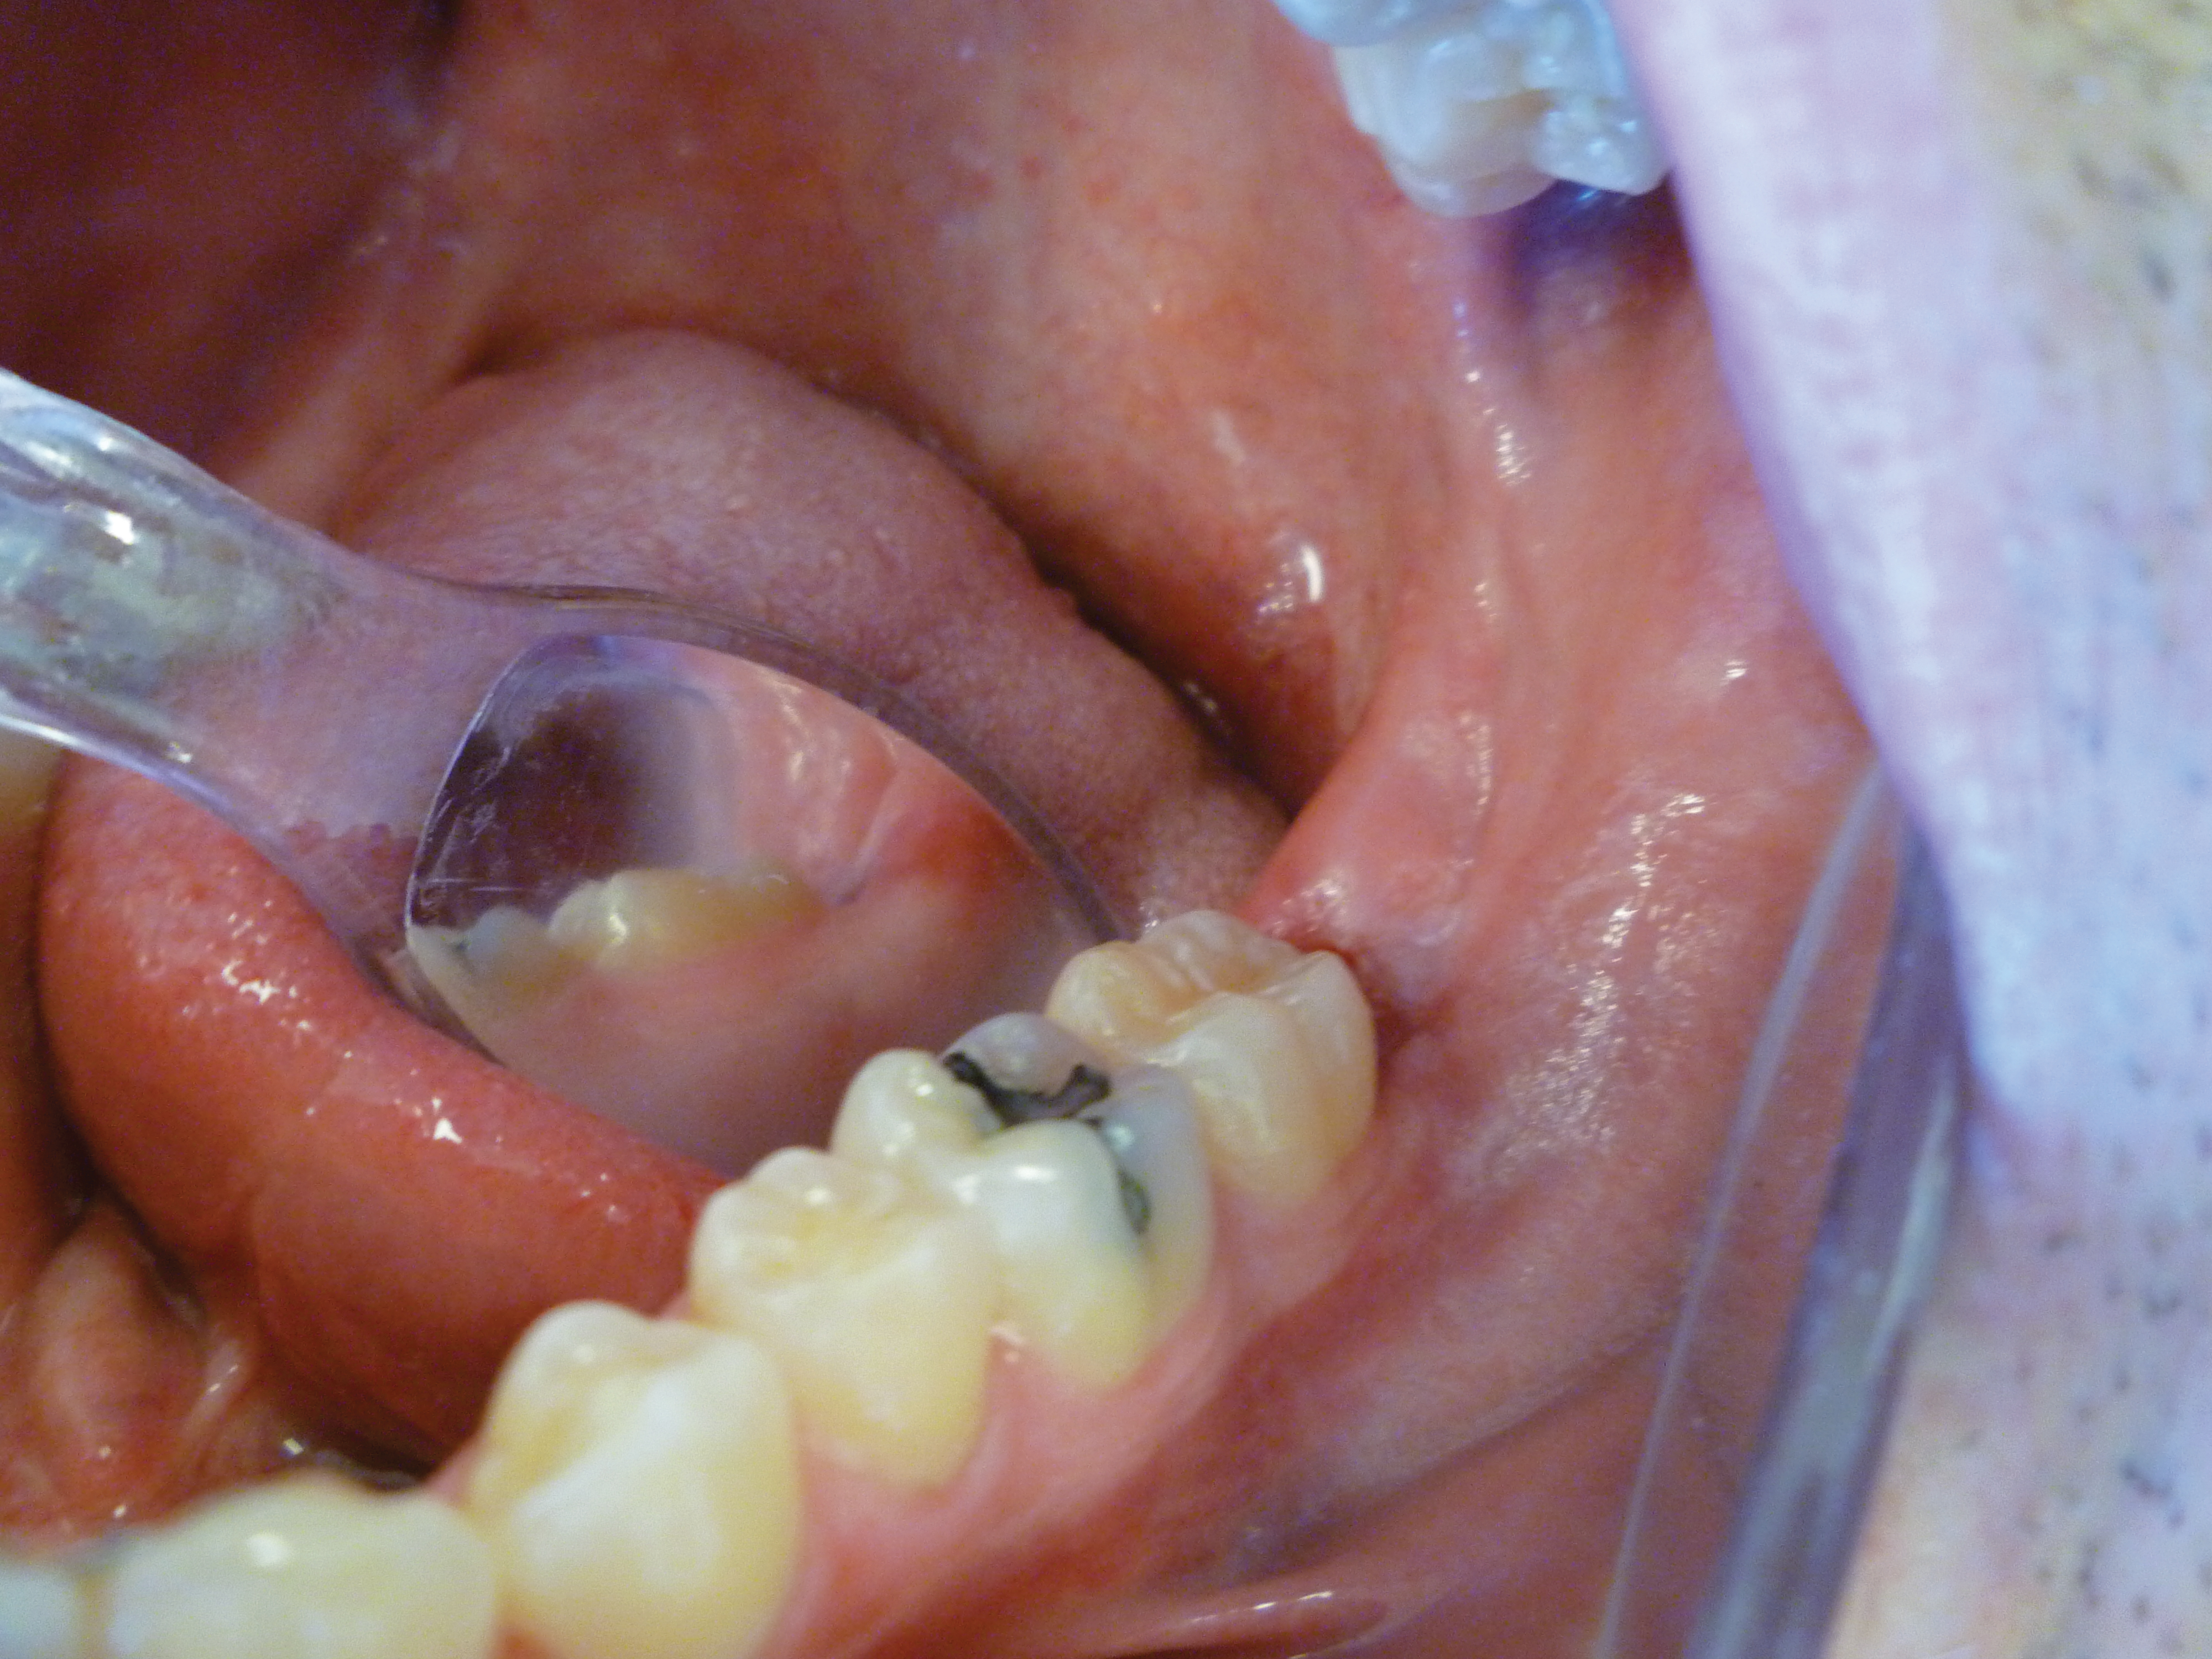

4. Additional tissue around the primary surgical site was superficially ablated to “feather out” the wound and make the treated area blend with the healthy gingiva better (Figure 7).

Fig 7. Immediate postoperative view. Additional tissue was ablated to make the ablated area blend with the surrounding tissue better. No suturing or dressing was required due to the hemostasis obtained with the CO2 laser.

Figure 7